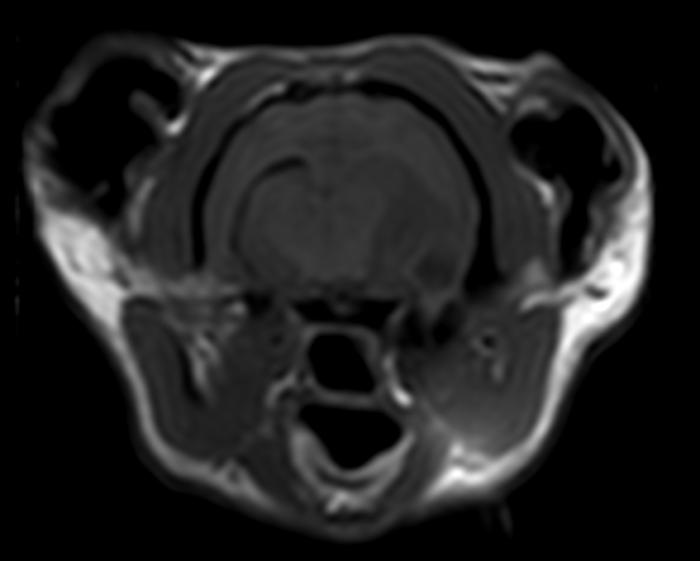

- Resonancia magnética craneal: (día 5) ocupación completa de la cavidad timpánica izquierda (Figura 1A-F) con invasión intracraneal (Figura 1A-C) con edema vasogénico y efecto masa con desplazamiento dorso-medial del lóbulo piriforme, desplazamiento contralateral de la línea media y región talámica izquierda (Figura 1A,D), colapso marcado del ventrículo lateral izquierdo (Figura 1F), y signos de herniación transtentorial e incipiente transforaminal. Se sospecha de infección intracraneal otogénica con formación de absceso en región temporal por extensión de otitis media-interna. Cabe señalar que no se visualizó contenido en las bullas timpánicas.